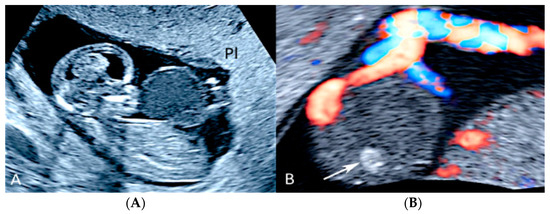

3.1.5. Placental Mesenchymal Dysplasia